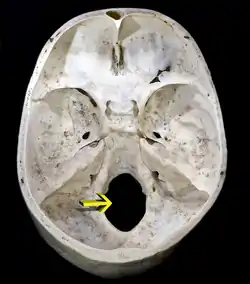

سوراخ پس سری (به انگلیسی: Foramen Magnum) در کالبدشناسی، به حفره ای بزرگ در استخوان پسسری جمجمهٔ انسان گفته می شود. این یکی از چندین بازشدگی دایروی یا بیضوی شکل است که در جمجمهٔ انسان وجود دارد و از طریق آن پیاز مغز به جمجمه وارد می شود.

سوراخ پس سری (پایین شکل)